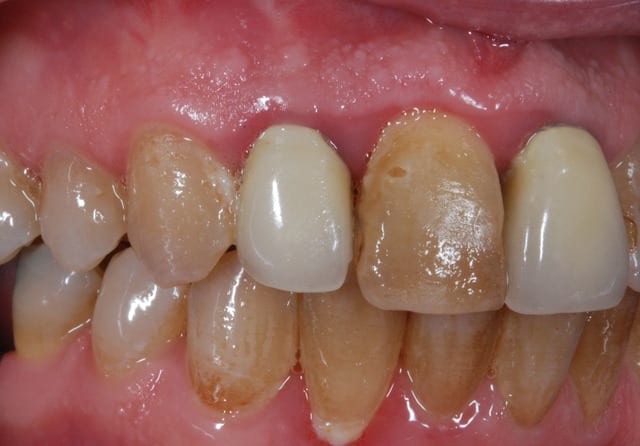

beau travail, mais

les 2 cas ne me semblent pas comparable dans la mesure ou tu as réussi à préserver un bandeau d'os vestibulaire presque au niveau des collets. Il permet un effet piquet de tente incomparable et évite les mauvaises surprises de perte importante de volume de biomat a la cicatrisation.

Dans l'autre cas la table vestibulaire est manquante, le résultat d'une EII beaucoup moins prévisible et dans un secteur esthétique j'aime pas jouer a la roulette russe.